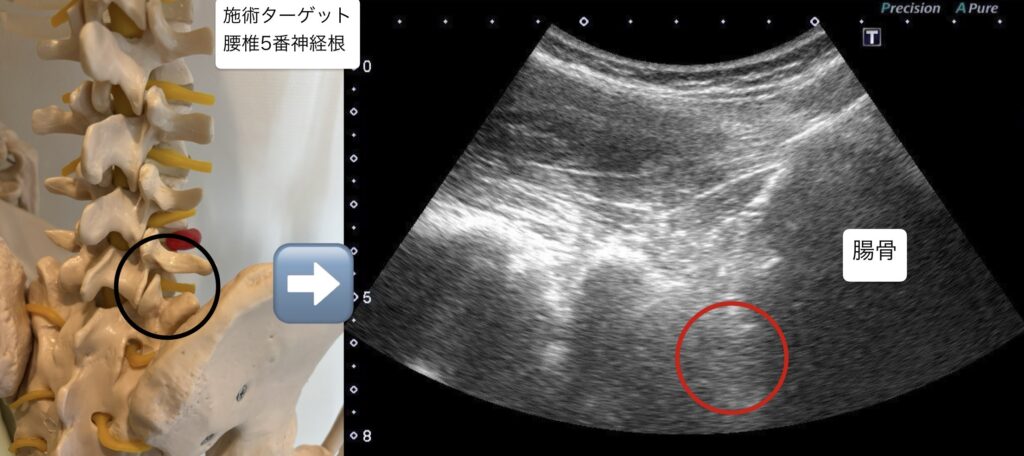

・腰椎5番神経根に対し、超音波エコーガイド下で鍼通電を行った。